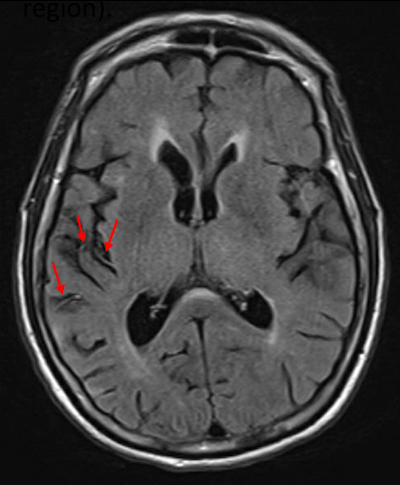

Abstract Body: Both left hemisphere (LH) and right hemisphere (RH) stroke can cause contralesional viewer-centered neglect (VCN) or stimulus-centered neglect (SCN). Studies using perfusion imaging have shown that in acute stroke, hypoperfusion beyond the infarct contributes to deficits, including neglect. However, perfusion imaging is not always available. FLAIR hyperintense vessel (FHV; Fig. 1) number and site estimate the volume and site of hypoperfusion. We hypothesized that FHV rating in the right parietal cortex would contribute to VCN.

A series of 256 consenting acute stroke patients (82 LH and 174 RH) completed a neglect task with 30 ovals – 10 full, 10 with a gap on the left, and 10 with a gap on the right. Patients were asked to circle full ovals and cross out ovals with a gap on either side. We defined VCN as >10% of ovals unmarked after the most extreme mark (Fig. 2), and SCN as neglecting or incorrectly marking >10% of contralesional gaps (Fig. 3). On FLAIR sequences, we identified FHVs in 4 MCA regions: frontal, temporal, parietal, and insular, as well as ACA and PCA territories. Each region was scored from 0 to 2: 0 = no FHVs; 1 = 1-2 FHVs on 1-2 slices; 2 = 3 or more vessels on 1 slice or 3 or more slices with at least 1 FHV (total=0-12). Infarct volume was calculated after manual tracing of lesions on DWI. We used multivariable logistic regression, with the presence of VCN or SCN as the dependent variable, and FHV ratings in each territory, infarct volume, and age as independent variables. We used chi squared tests to test associations between dichotomous variables.